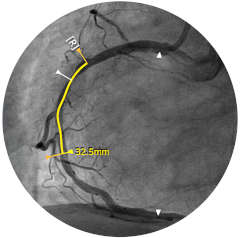

Abbildung 1

Abbildung 2